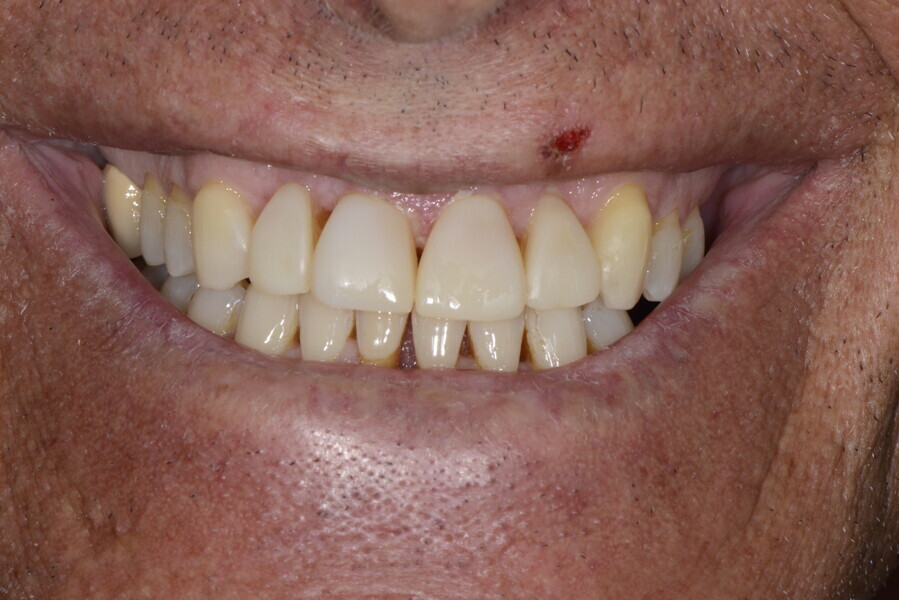

The 58-year-old patient wished to improve his oral aesthetics and function, complaining of mobility of the posterior teeth and wear of the anterior teeth. After data collection, a very complex situation was identified (Figs. 11–13):

1. severe periodontitis with poor prognosis of some teeth;

2. anterior crossbite;

3. severe wear mainly of the anterior teeth and compensatory eruption;38

4. atypical swallowing and lower posture of the tongue at rest;

5. masticatory dysfunction during the mastication test; and

6. no significant signs of temporomandibular disorder.